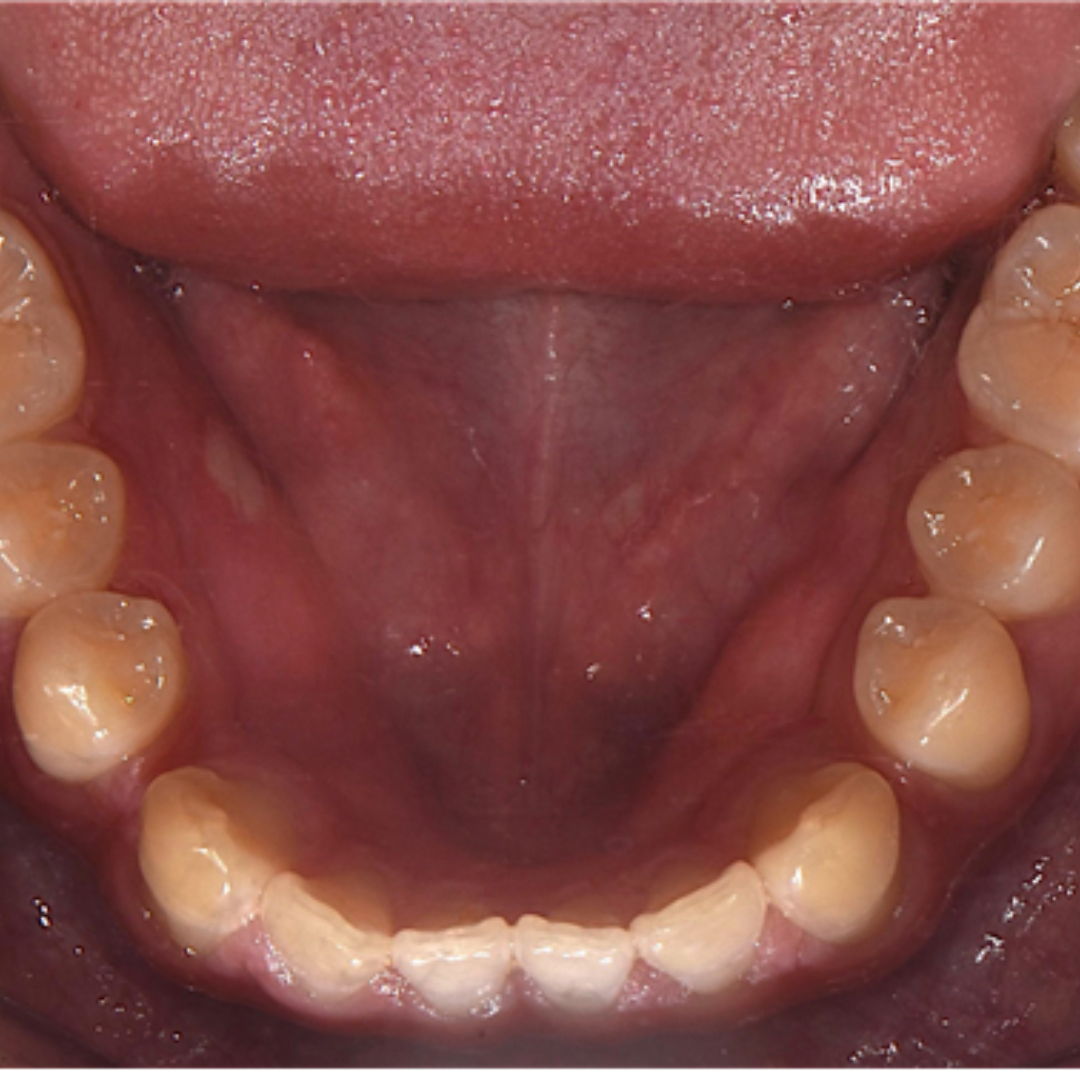

앞니 사이 벌어진 공간과 정중선 불일치를 고민으로 내원하셨던 20대 남성 환자분입니다. 윗니, 아랫니 공간이 각각 3.4mm, 2.6mm 가량 벌어져있고, 위와 아래의 중앙선 차이가 2.1mm 정도로, 상대적으로 정중이개와 정중선 불일치가 눈에 띄는 모습입니다. 해당 환자분께서는 격투기를 취미로 하시는 분이셔서 교정장치를 부착한 채로 얼굴 부위에 타격이 있을 경우 입 안이 다칠까봐 걱정이 있으셨습니다. 교정 진단 상담 후 고민 끝에 부상 방지를 위해 표면이 매끈한 투명교정 장치로 치료하시기로 결정하셨습니다.

최근에는 티 나지 않는 교정을 원하시는 심미적인 이유 뿐만 아니라, 위생 관리, 음식물 섭취, 부상 방지 등 다양한 이유로 전통적인 부착식 교정장치 대신 투명 교정을 선택하시는 환자분들이 부쩍 많아지셨습니다. 투명 교정 치료는 결과는 동일하면서 사진 촬영, 운동, 여행 등 일상 생활에 제약이 크게 없다는 점이 큰 장점입니다. 다만, 증례에 따라 부착식 교정장치가 더 빠르고 효과적인 경우도 있어 교정 치료 전 전문의와의 상담을 통해 결정하는 것이 좋습니다. ^^ 총 32주 간의 교정 치료가 종료된 모습입니다. 기존에 가장 고민이셨던 공간 벌어짐, 정중선 불일치가 예쁘게 수정되었습니다. 2025.5.18.

치료 전, 후 미소가 눈에 띄게 개선되었습니다. 정면에서 두드러지게 보였던 정중 이개와 정중선 불일치가, 벌어진 공간이 폐쇄되고 가지런하게 배열되니 깔끔하고 정돈된 인상을 줍니다. 앞니의 벌어진 공간 폐쇄를 위해 라미네이트나 크라운 치료로 심미적이고 즉각적인 개선을 가져오는 경우도 있습니다. 하지만 위 환자분의 경우 다른 부정교합이 있기 때문에 교정 치료 없이 심미 보철을 진행했다면, 정중선 불일치가 잔존하거나, 앞니 크기가 비대칭적으로 마무리되었을 수 있습니다. 32주의 교정 치료로 자연스럽고 아름다운 미소를 회복하여 환자분도, 의료진도 만족한 결과를 얻어 성공적인 투명 교정 치료 증례로 소개드렸습니다. 세심한 진단과 맞춤형 치료계획으로 예쁜 미소를 찾아드립니다! 안전한 365서울앞선치과 교정 치료 많은 관심 부탁드립니다~!!

치료 전, 후 미소가 눈에 띄게 개선되었습니다. 정면에서 두드러지게 보였던 정중 이개와 정중선 불일치가, 벌어진 공간이 폐쇄되고 가지런하게 배열되니 깔끔하고 정돈된 인상을 줍니다. 앞니의 벌어진 공간 폐쇄를 위해 라미네이트나 크라운 치료로 심미적이고 즉각적인 개선을 가져오는 경우도 있습니다. 하지만 위 환자분의 경우 다른 부정교합이 있기 때문에 교정 치료 없이 심미 보철을 진행했다면, 정중선 불일치가 잔존하거나, 앞니 크기가 비대칭적으로 마무리되었을 수 있습니다. 32주의 교정 치료로 자연스럽고 아름다운 미소를 회복하여 환자분도, 의료진도 만족한 결과를 얻어 성공적인 투명 교정 치료 증례로 소개드렸습니다. 세심한 진단과 맞춤형 치료계획으로 예쁜 미소를 찾아드립니다! 안전한 365서울앞선치과 교정 치료 많은 관심 부탁드립니다~!! |